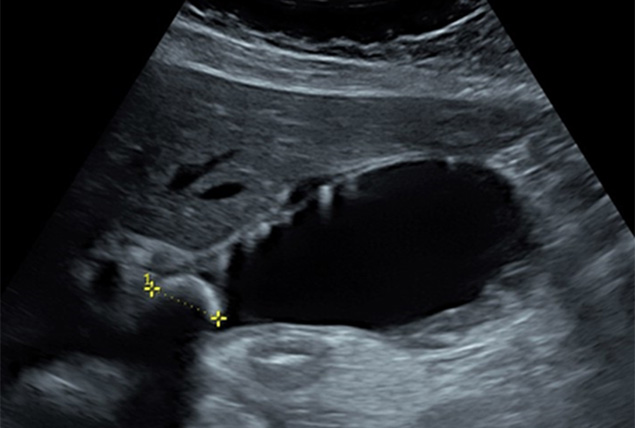

Abdominal Ultrasound

- Extended normal anatomy: liver, gallbladder, pancreas, spleen, kidneys, pelvis, large vessels and bowel

- Recognising common pitfalls

- Understanding the limits of abdominal PoCUS